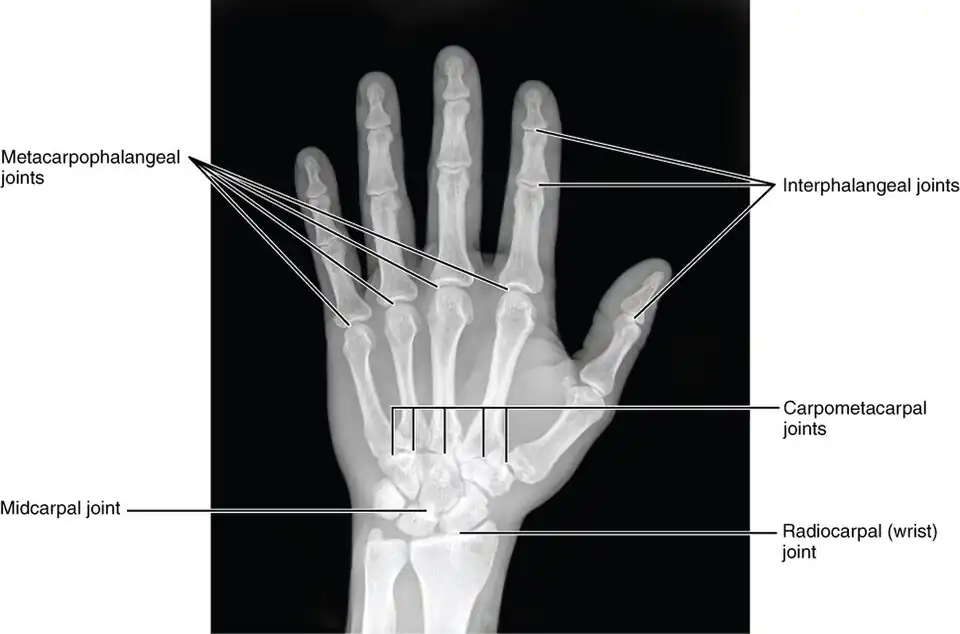

Interphalangeal joints of the hand

The interphalangeal joints of the hand are the hinge joints between the phalanges of the fingers that provide flexion towards the palm of the hand.

There are two sets in each finger (except in the thumb, which has only one joint):

- "proximal interphalangeal joints" (PIJ or PIP), those between the first (also called proximal) and second (intermediate) phalanges

- "distal interphalangeal joints" (DIJ or DIP), those between the second (intermediate) and third (distal) phalanges